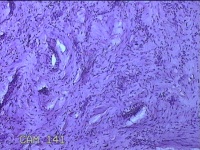

舌头肿物

性别

女

年龄

25岁

临床诊断

一般病史

无

标本名称

大体所见

灰白粉红色肿物0.7x0.5x0.2cm一个,表面光滑。

图2

纤维性息肉